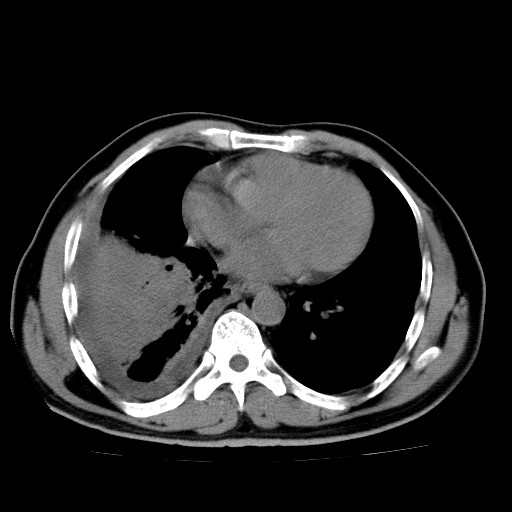

男,54岁,咳嗽,右侧胸痛10天。肺窗>150k,传不了

右中央型肺癌并右肺下叶不张,纵隔内及右胸膜转移,右胸腔积液

考虑   右肺癌伴右下肺部分不张,阻塞性肺炎,纵隔淋巴结增大,右侧胸腔积液其他待排

右下叶大片实变,肺门未见明显肿块影。有胸腔积液和纵隔内肿大淋巴结影。没有增强和肺窗,不好定。

右下叶大片性阻塞性肺炎,肺门未见明显肿块影,纵隔内可见肿大淋巴结影,右见右侧胸腔积液及右侧胸膜增厚。

考虑:右侧中心性肺癌?伴纵隔淋巴结转移。建议上传肺窗。